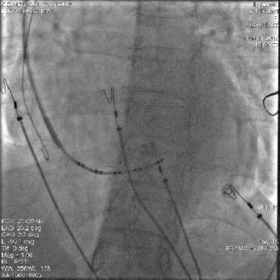

经长鞘直接造影确定鞘管位置

造影示鞘管已经超选进入后静脉,不在冠状窦主干内,同时侧静脉及冠状静脉主干显影。可见冠状静脉主干向上,走形角度较大

“双泥鳅”法进入冠状窦主干

将一根泥鳅留在后静脉内作为支撑,回撤长鞘至冠状窦口,使用另一根泥鳅按造影显示进入冠状窦主干

将长鞘送入冠状窦主干

顺利找到冠状窦主干,将两根泥鳅都送入主干内加强支撑,再送入长鞘